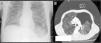

Tras 2 semanas de ventilación mecánica en la UCI, una radiografía de tórax ordinaria mostró un aumento de la hiperclaridad (signo del surco profundo) en la base del pulmón izquierdo, con un colapso asociado. Había también una depresión del hemidiafragma izquierdo. Se identificó una línea pleural visible en la región apical del pulmón izquierdo (fig. 1A). En ese momento el paciente estaba asintomático y hemodinámicamente estable. Recibía ventilación mecánica con control de volumen, con una presión teleespiratoria positiva (PEEP) de 10cmH2O. Se realizó una TC de tórax (fig. 1B) para completar la evaluación, y se observó que se había producido un gran neumotórax izquierdo, que se trató con éxito mediante la introducción de un drenaje torácico intercostal.